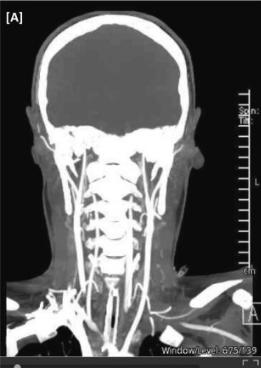

图4、CTA颅内血管造影

入院第5天,患者瞳孔固定放大,脑干反射缺失。脑干死亡的先决条件通过暂停镇静和抗癫痫药物得到满足,脑干死亡通过呼吸暂停试验和CT颅内血管造影无脑血流证实(图4)。患者的父母及其未婚夫从入院开始就已被告知,由于这种毁灭性的诊断和尽管有治疗但仍高的死亡率;双方同意退出治疗,患者在MICU去世。